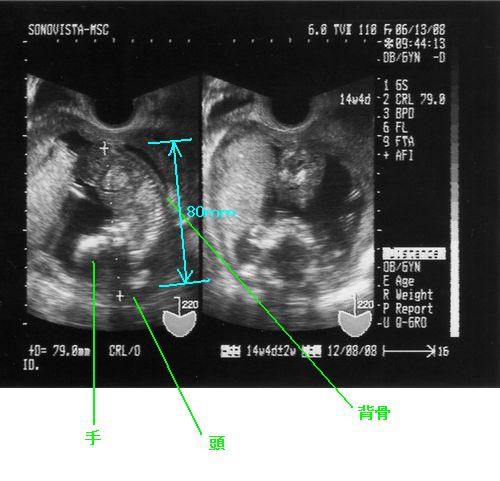

前回(12週目)の検診の時は身長が約40mm、手足もドラエモン状態だったのに対し今回の検診では身長が約80mmに伸び手足もより人間に近い形になってきているようです。

そしてもう一つのエコー写真ですが、緑の四角で囲ったところにエイリアンともターミネータとも見てとれる形がありますが、まぎれもなく正面から見た顔なんです。

この写真では分かりづらいですが、色々と角度を変えて見てみると頭蓋骨の形が少しいびつで蒼盾の頭の形とそっくりらしいんですよw